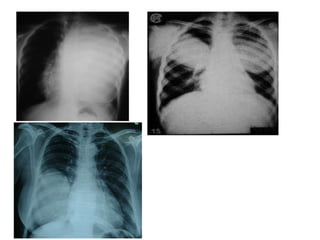

• Variable suivant le stade KH, 6 stades

( I = KHP non rompu : boulet de canon,opacités multiples

II à VI = KHP rompu : pneumokyste, nenuphar, bulles

DDB,coquille d’œuf…)

STADE EVOLUTIF DU khp

• Stade I : KH non rompu ( ds 50 à 70%) ,

asymptomatique

Opacité homogène ronde ,ovalaire de tonalité

hydrique

A contours nets comme tracé au compas

En boule de canon , ou parfois bilobée en

brioche,réniforme, polycyclique variable avec

le diamètre (hémithorax opaque avec culs de

sac costodiaphrarmatique libre)

Opacités multiples,parfois lachée de ballon

• Stade II , retrouvé ds 11,2% des cas,

Fissuration, hémoptysie, :

Ménisque gazeux situé au pole supérieur de

l’opacité entre la paroi externe du kyste et la

paroi interne du périkyste.

Image de pneumokyste

Évolution: surinfection espace périkystique

• Stade III, rupture, vomique:

Cavité aérique à paroi épaissie avec une

bronche de drainage

Rarement observé radiologiquement